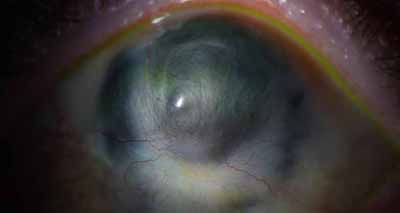

Superficie corneal irregular y grisácea

Opacidades granulares en parche

Perineuritis

- Superficie corneal irregular y grisacea

- Opacidades granulares en parche

- Formación de lineas epiteliales elevadas de aspecto granular, que pueden dar imágen de seudodendritas

- Opacidades superficiales satélites

- Ulceración epitelial variante

- Formación de anillo inmunológico